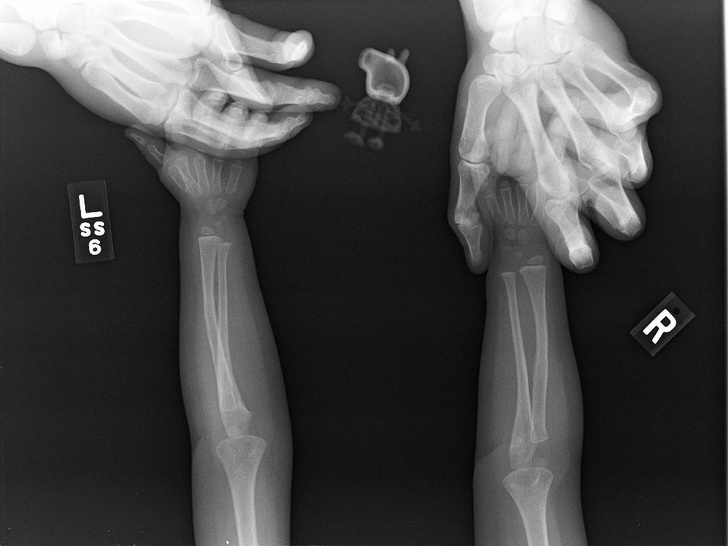

11. Так змінюється рука дитини з віком

На місці деяких кісток спочатку розташовуються хрящі, які пізніше замінить кісткова тканина.